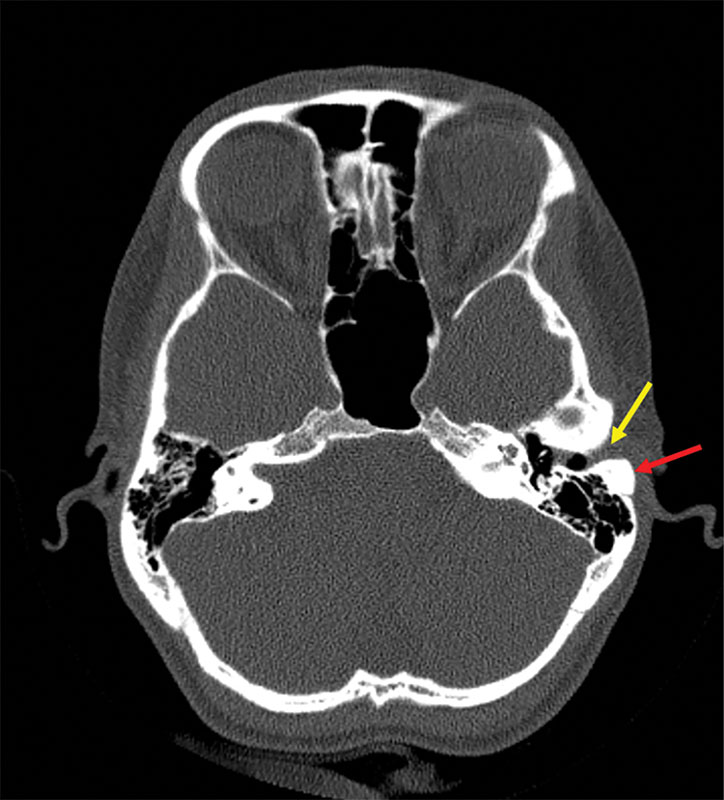

Рис. 2. Данные компьютерной томографии височных костей пациентки Ш.: сосцевидные отростки пневматического типа строения, барабанная полость и антрум свободны, красная стрелка указывает на новообразование сосцевидного отростка

Заключение по данным спиральной компьютерной томографии (СКТ) височных костей от 03.10.2023 г. Левое ухо: сосцевидный отросток – на границе со входом в наружном слуховом проходе визуализируется образование костной плотности, овальной формы, размером 2 на 1,5 см; барабанная полость без патологии (рис. 2).